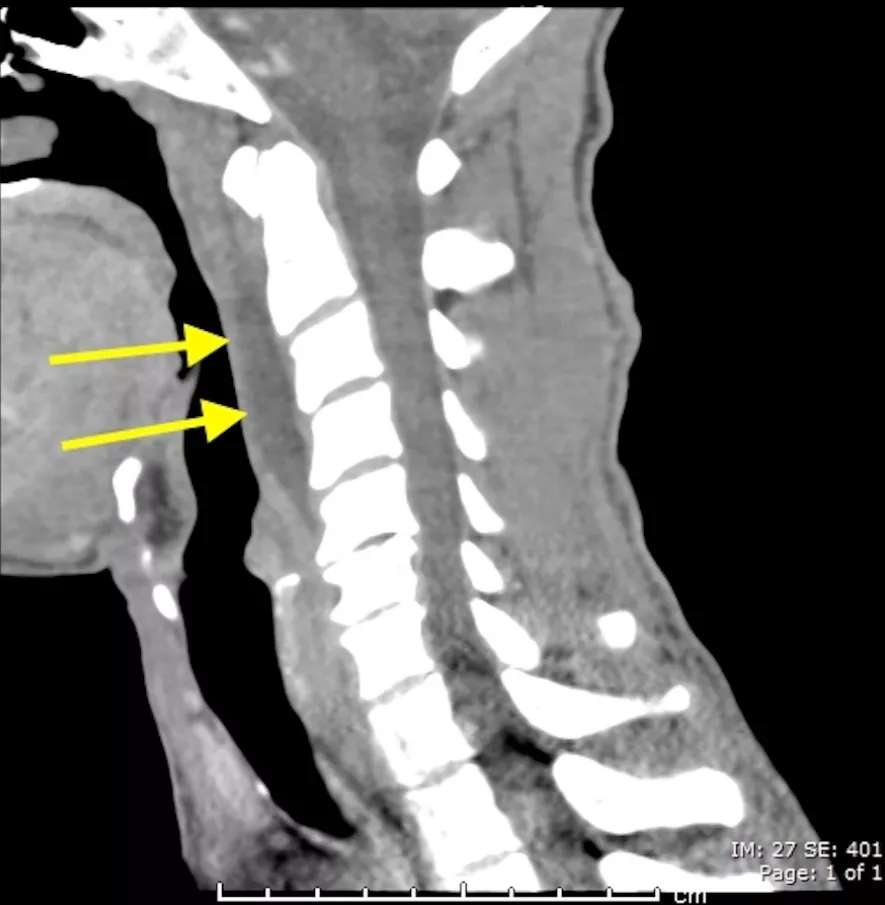

明确诊断主要通过典型的临床表现结合影像学方法,颈椎CT是关键。颈长肌钙化性肌腱炎特异性的影像表现是C1-4椎体前缘软组织肿胀和积液与C1椎体前弓下方不规则钙化沉着共存。

C1椎体前弓下方不规则钙化沉着

椎前积液和C1椎体前弓下方不规则钙化沉着

CT的高分辨率能够明确肌腱内的钙化,能够明确是钙化而不是其他骨骼来源的高密度影。钙化一般位于寰椎前弓的下方和枢椎齿状突的前方,少部分可位于下颈椎前侧。CT有助于明确椎体前积液的存在和排除其他病理表现,如骨折或脓肿。MRI对诊断不是必须,但有时可帮助确定软组织异常,排除咽后脓肿,脊椎炎或肿瘤。MRI检查T2加权在椎前可见局限性的裂隙样区域,大多位于C1-4水平,呈高信号改变,这反应是由于炎症引起的积液。T2加权、脂肪抑制序列和T1加权对鉴别积液和脂肪组织、含脂肪的骨髓以及咽后感染、脊椎炎有重要作用。MRI检查在钙化检查方面存在不足,T2加权呈低信号。